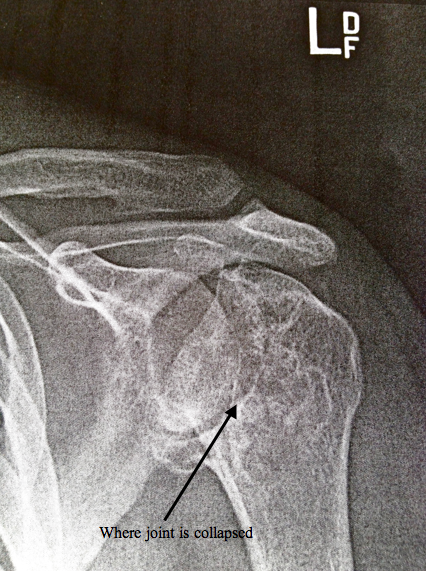

The Sharp specialist ordered a couple more x-rays so he could get an overhead view of my shoulder before I saw him last week. After a bit of a wait and a couple visits from his PA (physician assistant), the doctor came in and pulled up the x-rays. "I've never seen shoulders this degenerated before," he told my mom and I. Perfect, I thought bitterly to myself. It wasn't shaping up to be a good visit.

The doctor informed me that whereas the ball and socket joint normally forms a sort of ball and cup structure, my joints were so damaged that this structure had actually reversed to form a cup and ball. Due to this level of damage and because the bones were so worn away, he actually wasn't sure if he would be able to replace either shoulder at all. Normally the surgeon need a certain amount of bone in order for him to be able to do the replacement, but because of the severe degradation of the joints, the way it appeared from the x-rays, it would be next to impossible to do any of kind surgery. I can't say I was too pleased about that.

Again, as with the Sharp doctor, he told me just how bad my joints were and pointed out the structural reversal going on. He tossed around a few big words and drew some pictures on some paper and said most of the same things I'd heard exactly one week ago. However, the big different is that he didn't think it was unfixable. While the damage was extensive, there were ways of doing the surgery and getting the joints replaced.

The more damaged shoulder might be a candidate for a normal shoulder replacement, but the left one is shaped different and it would be extremely difficult to do a normal replacement with that. Instead, he talked about a surgery called a reverse shoulder replacement, which would, in effect, reverse the normal way the joint works, pivoting the head of the humerus (upper arm bone) around a shaped structure in place of the socket. The problem with doing this surgery is that it is a measure of last resort. Normally doctors like to use normal shoulder replacements first, and then use this when no other options is present. In fact, they don't really like doing this surgery on anyone under 70 because the joint wears out after 8-10 years and then it's iffy on what would be available to do next. The left one would almost certainly be a reverse, the right one too probably (although there's still a chance for a normal replacement).